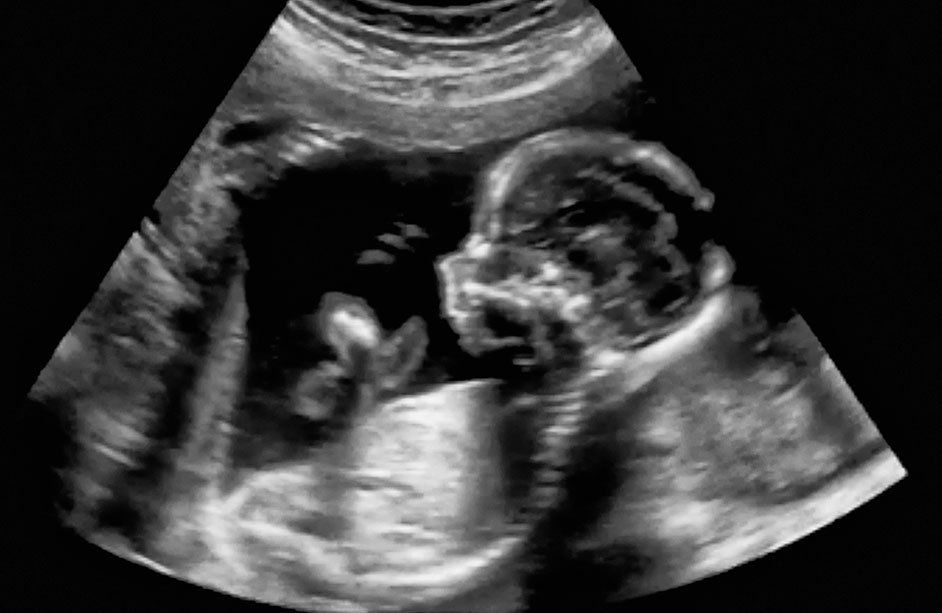

- Examen ecográfico de segundo y tercer trimestre (Obstétrica más perfil biofísico): Diagnóstico prenatal, valoración del crecimiento y bienestar fetal, edad gestacional, gestaciones múltiples, posición y situación fetal, frecuencia cardíaca fetal, medidas antropométricas del bebé, posición y estado de la placenta, volumen del líquido amniótico, cordón umbilical. Doppler de arterias y venas.

- Detalle anatómico o nivel III: Valoración del crecimiento y bienestar fetal descripción detallada de la anatomía del bebé, medidas antropométricas, huesos, Doppler fetal o perfil hemodinámico, Doppler de arterias y venas, valoración del flujo sanguíneo desde el útero a los órganos internos del bebé.